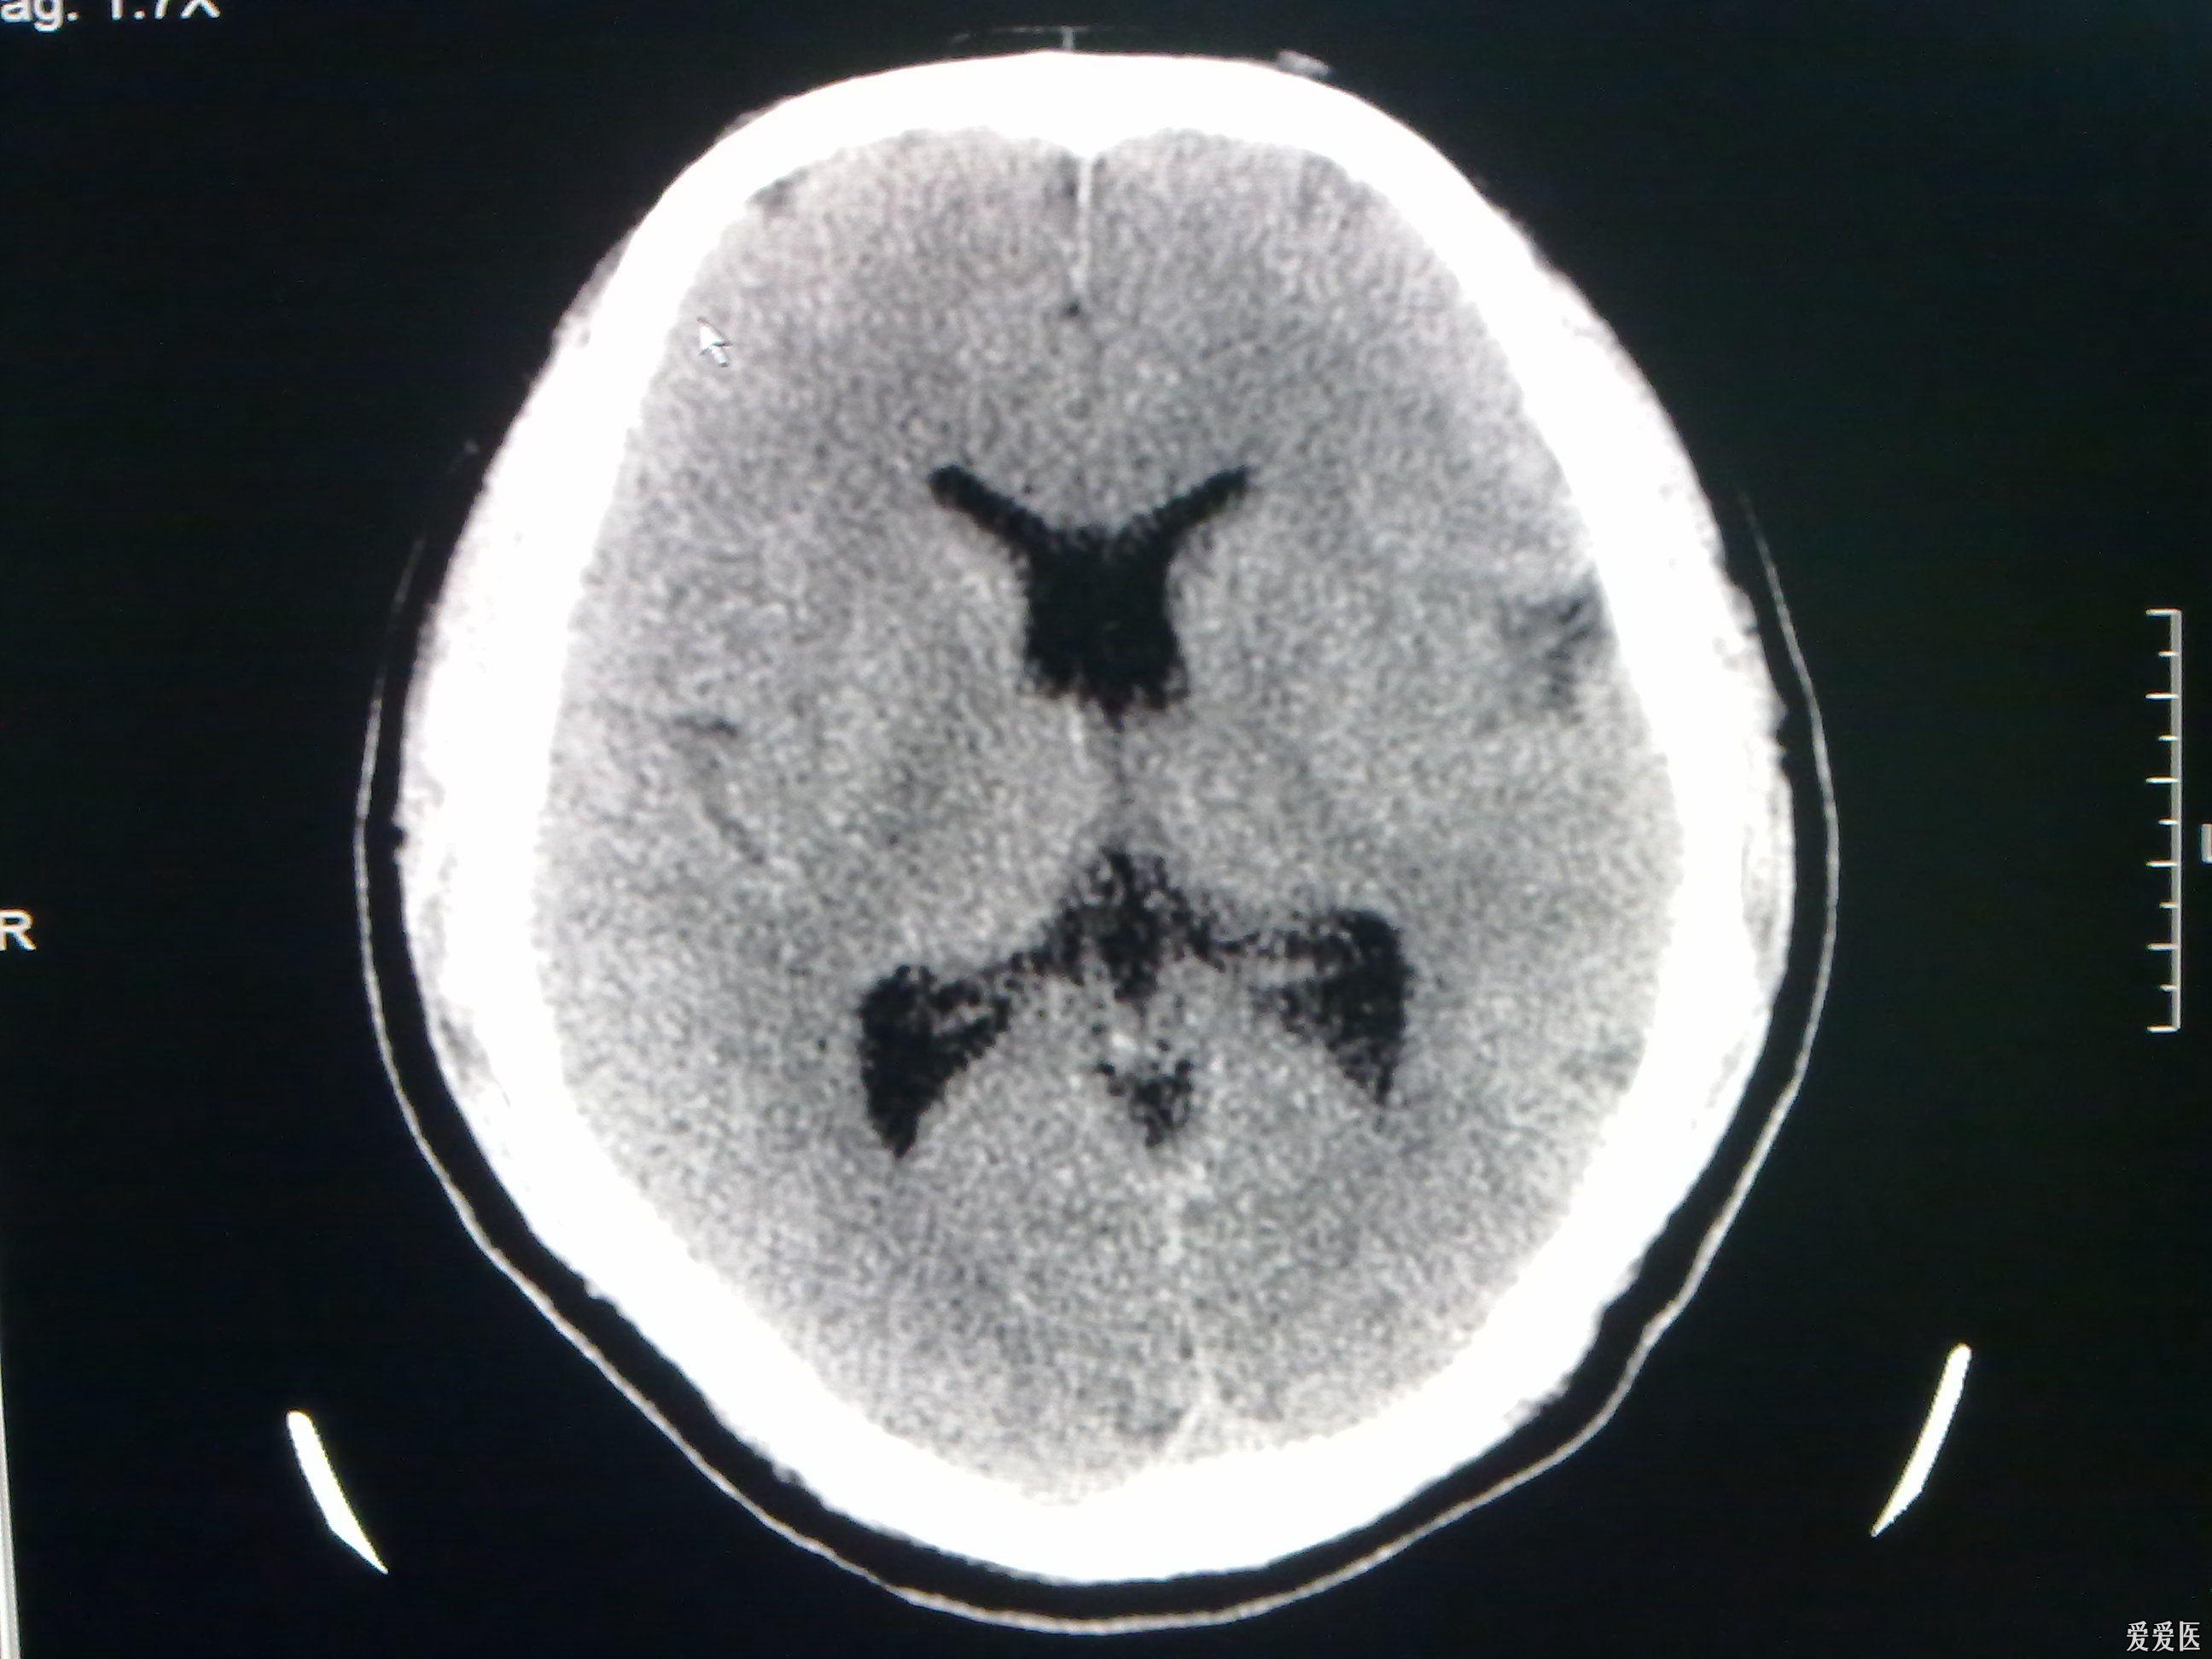

今天做到的病例脑裂畸形

图片尺寸2592x1944

今天做到的病例脑裂畸形

图片尺寸2592x1944

今天做到的病例脑裂畸形

图片尺寸2592x1944

今天做到的病例脑裂畸形

图片尺寸2592x1944